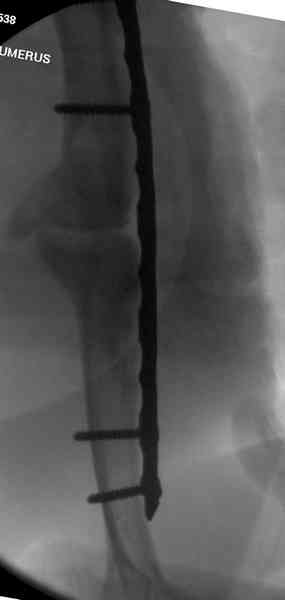

Хотя сам не стороннник применения более массивных имплантов для

плеча, но для этого случая сделали исключение. На снимке 4А диаметр

мягких ткани около 20 см, при весе больной более 135 кг, и также

выступление Андрея Волны подстегнуло к применению более массивной 4.5

мм локинг пластины.